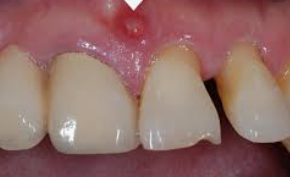

잇몸 질환은 많은 사람들이 경험하는 흔한 문제로, 적절한 치료와 관리를 통해 개선할 수 있습니다. 잇몸이 붓고 피가 나는 증상은 주로 치주 질환의 초기 신호로, 이는 치아를 지지하는 조직과 뼈에 염증이 생겨 발생합니다. 이러한 증상을 완화시키기 위해서는 구강 위생의 중요성을 인식하고, 정기적인 치과 방문을 통해 전문적인 조언을 구하는 것이 필요합니다. 또한, 영양소의 섭취가 전반적인 구강 건강에 미치는 영향을 고려하여, 비타민 C와 같은 항산화 영양소가 풍부한 식단을 유지하는 것이 도움이 됩니다. 오늘은 잇몸이 붓고 피날때 치료방법 및 영양제 추천에 대해 알려드리겠습니다.

잇몸 질환은 많은 사람들이 경험는 일반적인 문제로, 적절한 치료와 관리를 통해 개선할 수 있습니다. 잇몸이 붓고 피가 날 때, 이는 흔히 치주 질환의 초기 증상으로 볼 수 있으며, 이는 구강 위생 상태와 밀접한 관련이 있습니다. 이러한 증상을 완화하기 위해서는 정기적인 치과 검진과 함께 올바른 구강 위생 습관을 유지하는 것이 중요합니다. 또한, 특정 영양소의 섭취가 잇몸 건강에 긍정적인 영향을 미칠 수 있으므로, 영양제 선택에 있어서도 신중을 기해야 합니다. 이 글에서는 잇몸 부음과 출혈을 줄이는 데 도움이 되는 치료 방법과 영양제에 대해 자세히 알아보겠습니다.

잇몸이 붓고 피가 나는 증상은 흔히 잇몸 질환의 신호일 수 있습니다. 이러한 증상을 겪고 있다면, 가장 먼저 해야 할 일은 구강 위생을 철저히 하는 것입니다. 다음은 잇몸 붓기와 출혈을 줄이는 데 도움이 되는 몇 가지 방법입니다:

이러한 방법들을 통해 잇몸의 붓기와 출혈을 줄일 수 있지만, 증상이 지속되거나 악화될 경우에는 반드시 치과 의사와 상담해야 합니다. 잇몸 질환은 초기에 치료할수록 더 좋은 결과를 얻을 수 있으므로, 증상을 무시하지 말고 적극적으로 관리하는 것이 중요합니다.